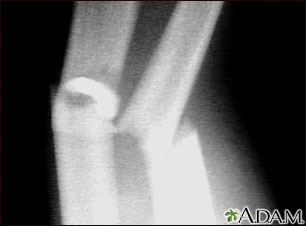

Esta radiografía muestra huesos del antebrazo (cúbito y radio) rotos (fracturados).